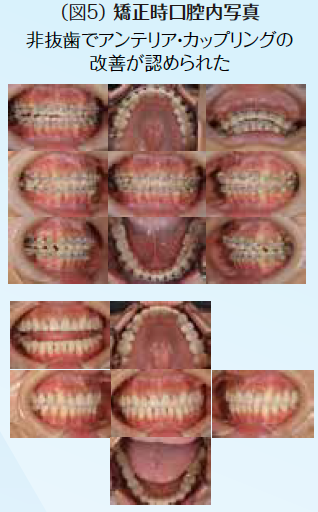

ブリッジの支台歯になっていたため応急処置として補綴装置は除去せず、そのままで抜髄処置を行なった。他に症状として右下7番の知覚過敏も呈していた。顎関節症状としても関節部に違和感があり、片頭痛も持ち併せているということで、病的咬合の疑いがあり、全顎的な診査・診断を行うこととした。10年前に母国韓国にて全顎的に審美修復がなされていたが、咬合面形態はかなり咬耗しバーティカル・ストップが喪失していた。アンテリアの状態も犬歯関係はⅢ級気味でアンテリア・カップリングが不良な状態で顎運動時に臼歯に負担がかかっていることが予測できた。前歯が無髄歯になった原因は審美修復をする際に便宜的に抜髄されたからである。臼歯部が抜髄に至った歯髄炎や既に無髄歯になっていて根尖部に病変が存在して再治療が必要な歯の病態に陥った原因は荷重負担によるものと推測できた。臼歯部における適正なバーティカル・ストップと咬頭干渉を起こさないために、アンテリア・カップリングの確保のために全顎矯正を含めた全顎的な咬合再構成を行うこととし、欠損部に関しては支台歯の負担軽減のためインプラントを用いた修復処置を計画した。

初期治療において炎症のコントロールを徹底するため、歯周治療と並行して、不良補綴装置を除去してプロビジョナル・レストレーションを装着し、感染根管歯は全て再治療を行なった。初期治療終了後、矯正治療を行なった。矯正学的診断が骨格性Ⅰ級で上下顎前突傾向があり、下顎前歯部の叢生によって犬歯関係はⅢ級関係を示していた。矯正治療を行うことで歯の位置関係が改善したことを確認したのち、確定外科をインプラント治療と合わせて行い、再評価の後に補綴処置を行なった。デジタル機器を用いることで機能的にも審美的にもまた患者の要求にも対応しやすくなった。補綴処置終了後再評価を行いメンテナンスに移行した。治療期間4年で術後4年近く経過したが、無髄歯の根尖周囲組織も有髄歯の歯髄の状態も良好に経過している。欠損部にインプラントを用いたことによってブリッジの支台歯になっていた無髄歯の予知性も向上したと考える。(図2〜図14)